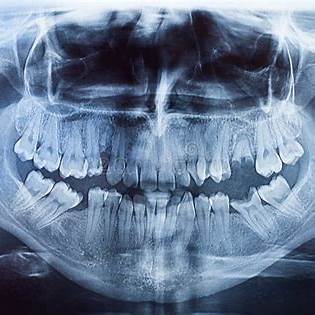

The medical assistant led me to an operating room, then sat me in front of a big-screen television with a giant skeletal image of my mouth. In the upper right, it read: “Rory Hughes: 46 years and 107 days old.”

Underneath, two alerts highlighted in red:

Family history of cancer.

Family history of mental problems.

My eyes were still fixed on the death screen, refusing to close—right up until the surgeon started twisting my tooth out like a stripped screw. Thanks to the Novocaine, I could only feel pressure as my head jerked, but I could hear squeaking and pulling and twisting.

Something happened as the doctor rooted around in my mouth while I gazed at that digital tombstone.